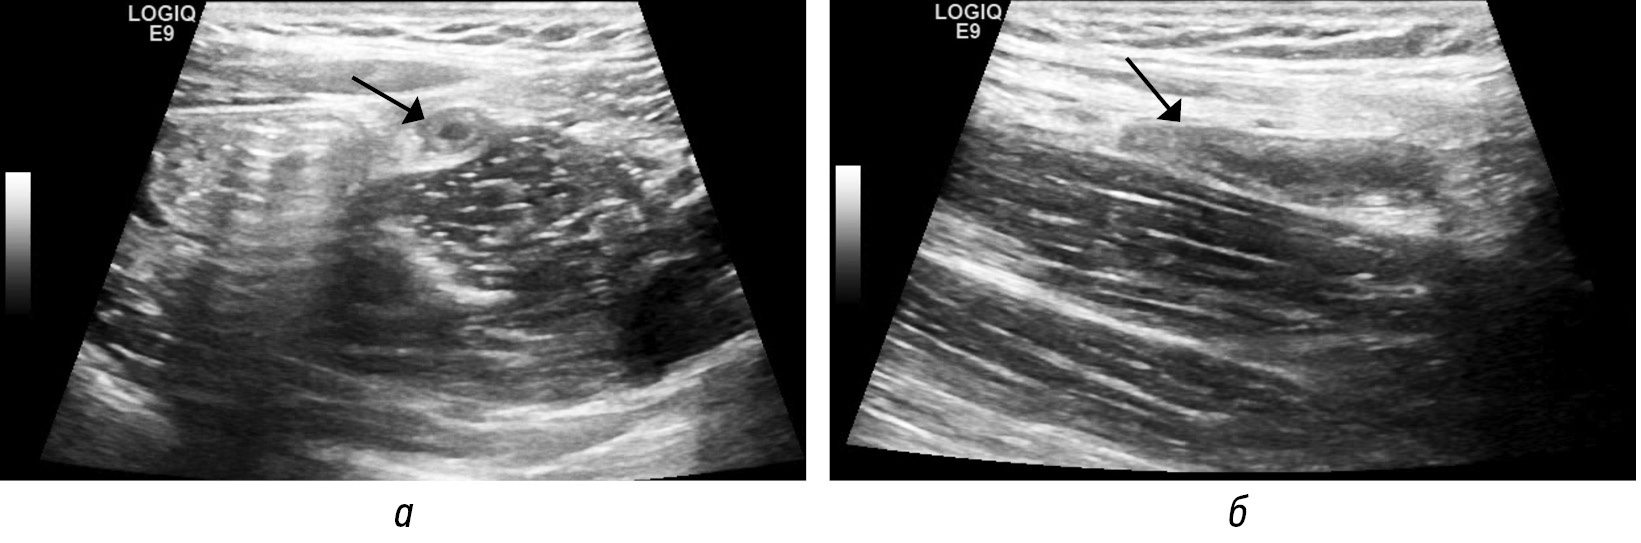

Рис. 8. Сонограммы в В-режиме (а — продольный скан аппендикса; б — поперечный скан аппендикса). Воспаленный аппендикс (стрелки) окружен воспаленной жировой тканью более высокой эхогенности

Fig. 8. B-mode sonograms (а — longitudinal scan of the appendix; б — transverse scan of the appendix). The inflamed appendix (arrows) is surrounded by inflamed adipose tissue of higher echogenicity

Рис. 9. На нативных КТ-томограммах в аксиальной (а) и фронтальной (б) плоскостях и соответствующих сонограммах (в, г) визуализируется аппендикс (стенки толщиной 4 мм, в просвете (до 6 мм) неоднородное содержимое) (стрелка) с отеком стенок слепой кишки (пунктирная стрелка). Прилежащая жировая клетчатка без видимых изменений

Fig. 9. On native CT-tomograms in the axial (а) and frontal (б) planes and corresponding sonograms (в, г), the appendix is visualized (walls 4 mm thick, in the lumen (up to 6 mm) heterogeneous contents) (arrow) with edema of the walls of the cecum (dotted arrow). Adjacent adipose tissue without visible changes